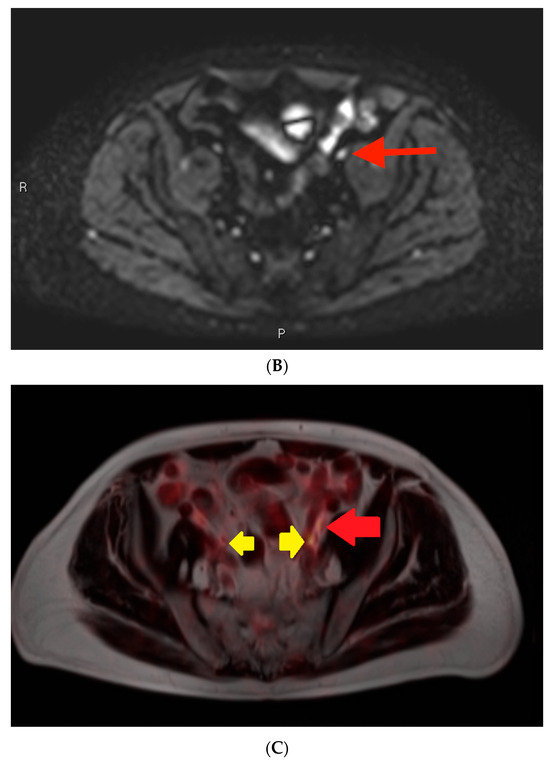

3.2. Example 2—Mischaracterization of Lymph Node Metastasis

Among the cases included in this analysis, there was only one example of a characterization issue, defined as an instance where a lymph node was suspicious on MRI on the basis of size but was not prospectively included in the report (Figure 4). This case involved a lymph node metastasis. The PSMA PET showed a PSMA-avid node in the left supraclavicular region (Figure 4C). The lymph node measured > 1.0 cm in short axis (Figure 4A). However, it also exhibited a benign morphology with an oval shape and a fatty hilum.

Post-contrast fat-saturated gradient T1-weighted image (A), diffusion-weighted imaging with b = 900 s/mm2 (DWI) (B), and fused PET/single-shot T2-weighted imaging (C) through the pelvis. In Figure 3A, the lesion is marked with measurement calipers. In Figure 3B,C, the lesion is denoted with a red arrow. Yellow arrows indicate the ureters, which show physiologic PSMA PET uptake.